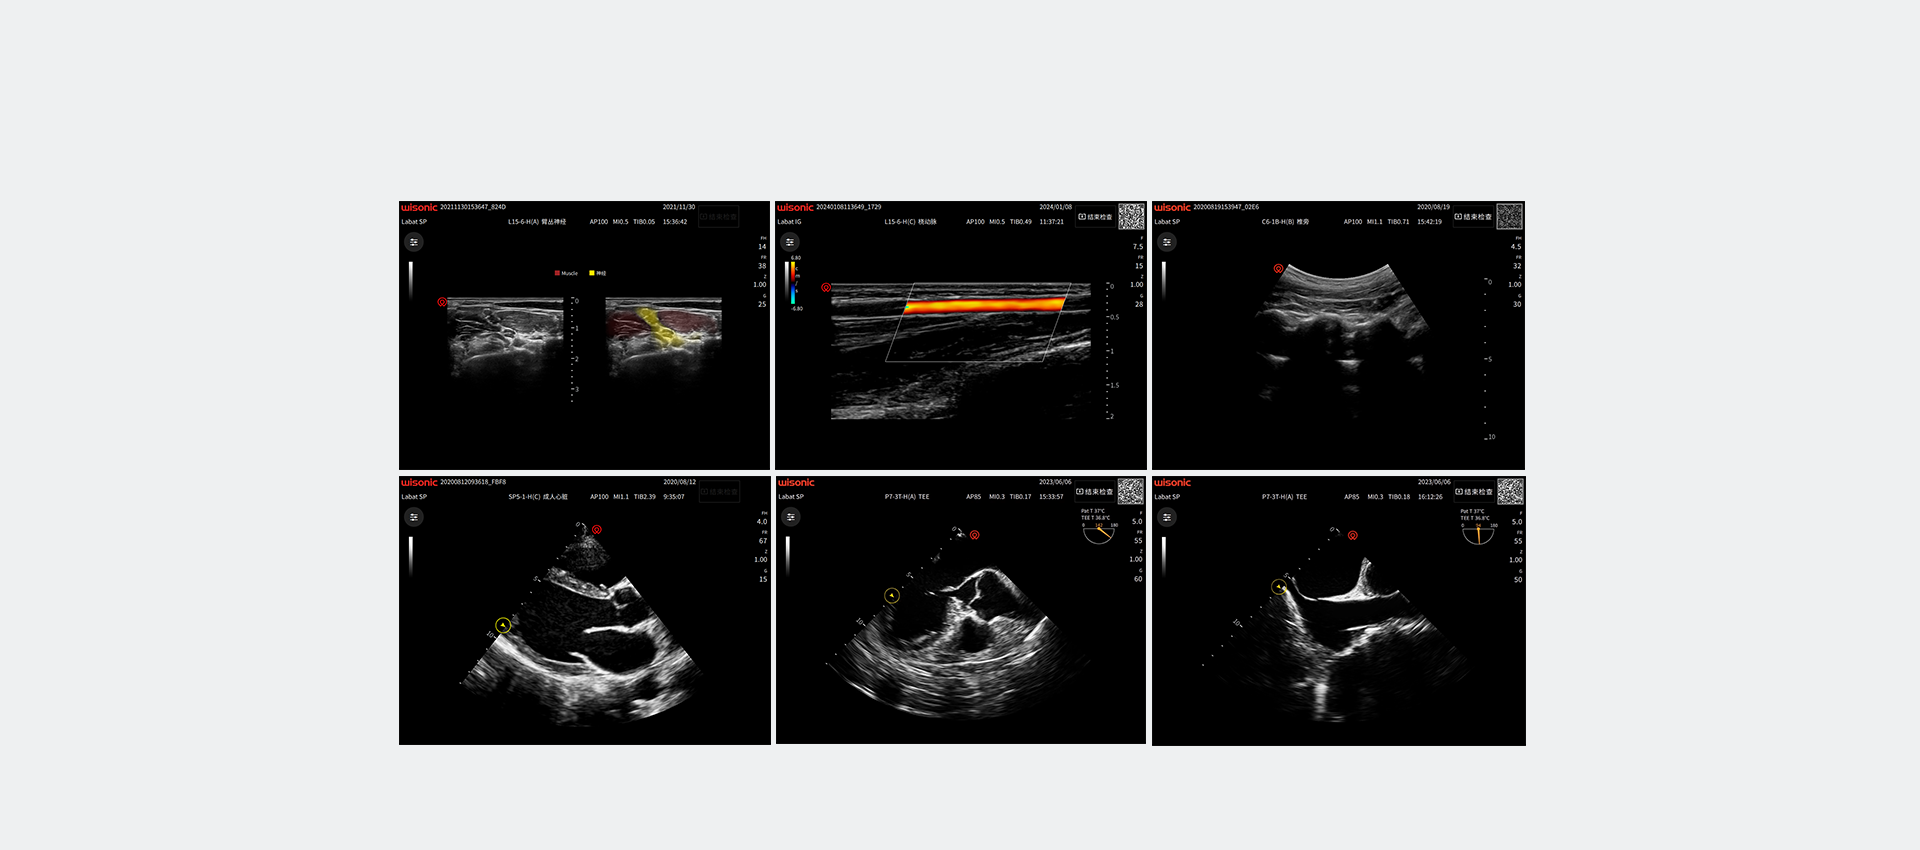

wiNerve

Reconocimiento inteligente de nervios AI

Reconocimiento en tiempo real

Solución en Cloud

Apoya múltiples nervios.

Excellent Clinical Images

Application pictures